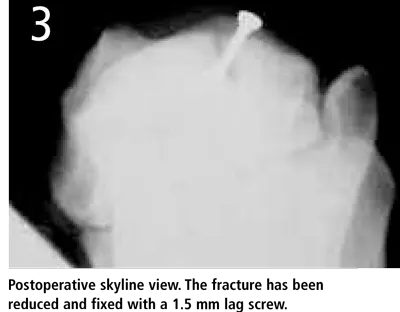

Diagnosis. The standard dorsopalmar, mediolateral, mediolateral flex, and dorsopalmar oblique radiographic views were not diagnostic; however, the palmaromedial dorsolateral hyperflexed oblique view identified a short fracture line with a subchondral defect affecting the dorsal articular margin of the radius (Figure 1). A skyline view (Figure 2) confirmed the diagnosis and established the exact location and size of the bone fragment.

In this case, open reduction and rigid, "gap-free" internal fixation was performed. The fracture was exposed with a small incision made directly between the extensor carpi radialis and the common digital extensor tendons. The fragment was reduced and fixed with a 1.5-mm lag screw (Figure 3). The head of the screw was countersunk to avoid irritation of the surrounding soft tissues or interferences with the proximal carpal bones during extension of the joint. After the surgery a light bandage was applied to the carpus for 10 days. After suture removal, a light bandage was reapplied for another 7 days and light exercise and physiotherapy were encouraged. Eight weeks after surgery, radiographs showed signs of bone healing. Ten weeks after the surgery, Sophie was back to full activity.